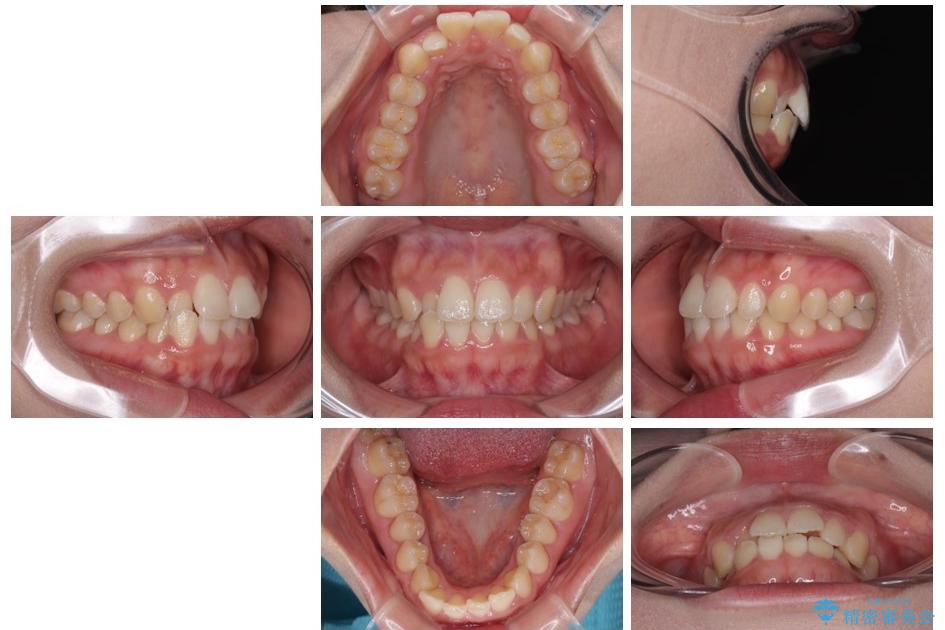

治療前

• 目立ちにくい表側装置で1年完了!狭いアーチを側方拡大し前歯のデコボコを整えた症例 治療前画像

前歯のデコボコが気になるでのことで来院された患者様です。

歯列アーチが狭くスペース不足により前歯がデコボコしている状態でした。見た目を改善しつつ、前歯を前方に突出させず、自然な笑顔を目指したいというご希望でした。